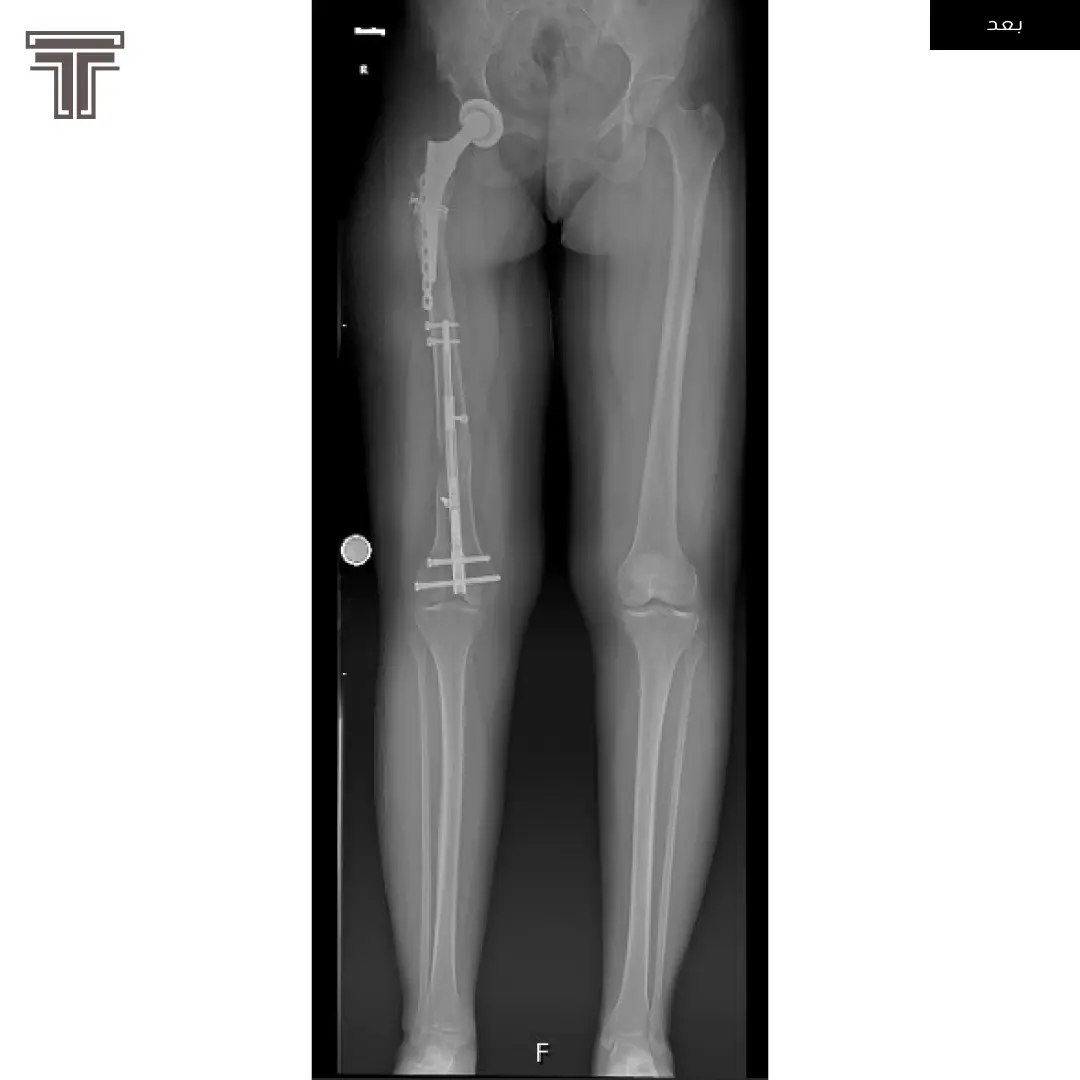

عندما تهمل خلوع الورك الولادية لعمر كبير يصبح علاجها وارجاعها صعب ويتطلب عملية استبدال للمفصل. وفي مثل هذه العمليات وتحديدا في استبدال مفاصل خلوع الورك الولادية يتطلب تقصير في طول الفخذ لتجنب المضاعفات.